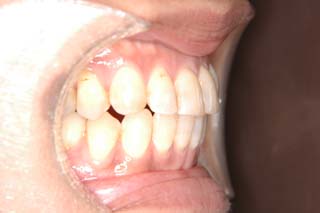

(開咬/叢生/非抜歯/リンガルブラケット矯正装置)

装置撤去です。動的処置は2年弱でした。十分とは言えない点もありますが、患者希望による非抜歯配列でしたので、概ね良好と言える結果が得られたと思います。まだ、オーソアンカー SMAPがそのまま残っているのが見えますが、もう必要ないので撤去して貰う予定です。今後は保定治療に移行し、咬合の安定状態を管理していきます。